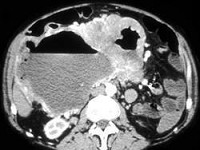

患者剧烈腹痛、腹胀,结合图像,最可能的诊断为()

A.卵巢癌

B.肠道肿瘤

C.出血

D.转移

E.以上都不是